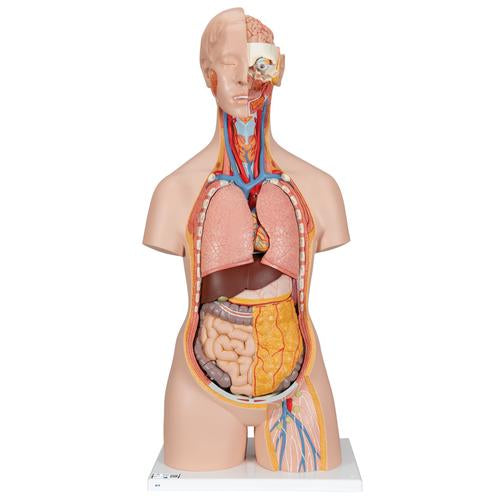

This meticulously crafted torso is expertly hand-painted with precision and made from high-quality plastic. All 3B torsos are designed and produced in Germany. This unisex human torso model features a distinctive open neck and back section extending from the cerebellum to the coccyx. It accurately depicts vertebrae, intervertebral discs, spinal cord, spinal nerves, vertebral arteries, and numerous other components in this vibrant representation of human anatomy. This human torso model includes the following detachable parts and organs:

- Removable 7th thoracic vertebra

- 6-part head

- Pair of lungs

- 2-part heart

- Stomach

- Liver with gall bladder

- 2-part intestinal tract

- Front section of kidney

- Front section of urinary bladder

Each organ in this human torso is hand-painted to ensure a high-quality product. This exceptional educational tool for human anatomy simplifies learning the placement of human organs. It is a